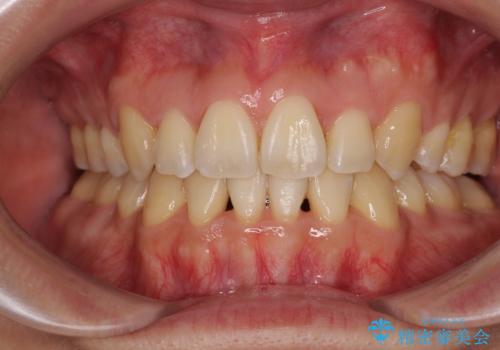

動きにくい歯はやはり動きにくく、咬み合わせ改善に時間を要しましたが、患者様には大変満足していただけました。